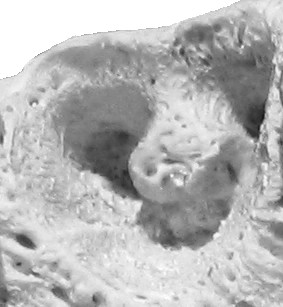

Alveola of the second premolar tooth in a bovine maxillary bone

Dental alveoli (singular alveolus) are sockets in the jaws in which the roots of teeth are held in the alveolar process with the periodontal ligament. The lay term for dental alveoli is tooth sockets. A joint that connects the roots of the teeth and the alveolus is called a gomphosis (plural gomphoses). Alveolar bone is the bone that surrounds the roots of the teeth forming bone sockets.